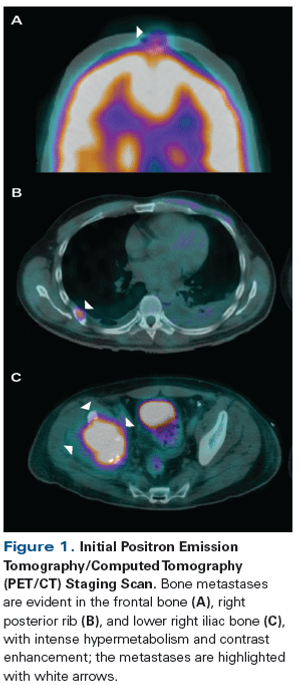

ByMaría T. Bourlon, MD, MSc, FASCO,Monica Meneses-Medina, MD,Sara Vázquez-Manjarrez, MD,Francisco M. Bustamante-Romero, MD,Adriana C. Gallegos-Garza, MD,Elaine T. Lam, MD A 42-year-old man presented with increasing right hip pain that limited his ability to walk. Magnetic resonance imaging (MRI) revealed a right lytic acetabular lesion. Further work-up included a computed tomography (CT) scan, which revealed an 8-cm left kidney tumor.